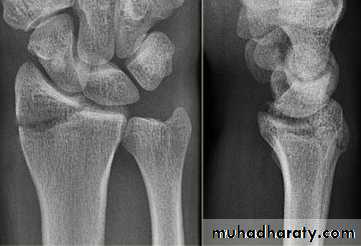

Avascular necrosis of proximal segment of scaphoid frac. non union fracture scaphoid

1- avascular necrosis :the proximal fragment may die especially with proximal pole fracture , it will appear

dense on x-ray .

2- non union : after 3 months if fracture not united it will be obvious that the fracture will not unite at all .